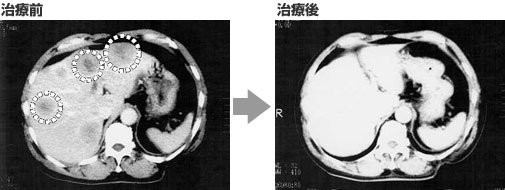

第一次复查后,医生说:如果你看一下影像片子,你可以看到令人惊讶的治疗结果。之前出现白色的病变部位,在两个月后消失到几乎看不见的程度。”

此外,王先生身体状况的恢复是显着的,不仅胸部疼痛消失,而且食欲也出现好转,能够自理很多事情。咳嗽和血凝块消失,痰液测试变为阴性。

治疗1个月后,肿瘤标志物AFP正常,半年后NSE和CEA正常。

高度活化的NK细胞联合化疗治疗开始一年后,不仅所有肿瘤标志物都正常,而且肺部肿瘤和肝脏肿瘤都消失了。